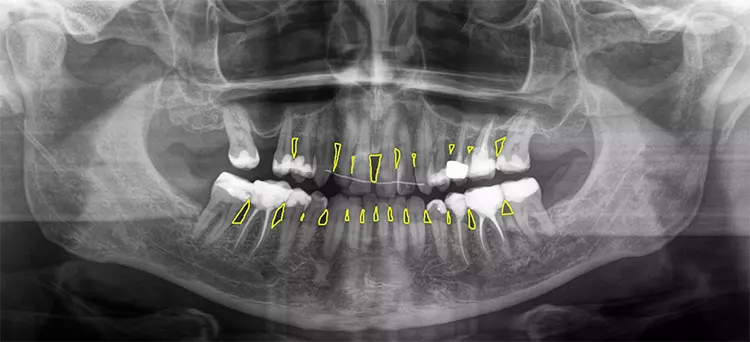

Dabei umfassen die ISO-Gruppengrößen 1 bis 3 jeweils zwei PHD-Werte, die Größen 4 bis 5 drei und die Größen 6 bis 7 fünf PHD-Werte. Alle Bürsten mit einem PHD von > 2,9 erhalten die ISO-Größe 8. Obwohl die neue Norm ein großer Fortschritt ist, führen die heterogenen ISO-Gruppengrößen vor allem bei größeren Interdentalraumbürsten zu ungenügender Differenzierung. Nicht alle Bürsten der gleichen ISO-Gruppengröße können denselben Interdentalraum passieren (Abb. 3). Entscheidend ist daher die Orientierung am einzelnen PHD-Wert und nicht an der ISO-Gruppengröße [28].